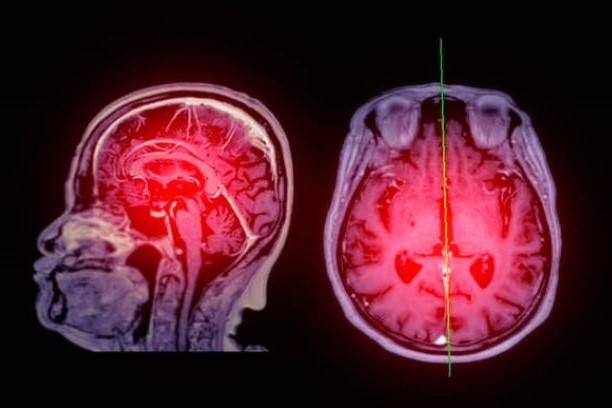

뇌경색은 뇌의 혈관이 막혀 뇌조직에 산소와 영양분이 제대로 공급되지 않아 발생하는 심각한 질환입니다. 특히 한국에서는 고령화와 함께 고혈압, 당뇨병 등 만성질환의 증가로 인해 뇌경색 환자의 수가 급격히 늘어나고 있습니다. 이는 일상생활에 큰 영향을 미치고, 적절한 초기 대응과 치료가 이루어지지 않으면 치명적인 후유증을 남길 수 있습니다. 따라서 뇌경색의 초기 증상을 정확히 파악하고, 적절한 치료 방법을 이해하며, 후유증을 최소화하기 위한 방법을 아는 것이 매우 중요합니다.

▌ 뇌경색의 초기 증상

뇌경색의 초기 증상은 개인마다 다르게 나타날 수 있지만, 대부분의 환자들이 공통적으로 경험하는 증상이 있습니다. 이러한 증상들은 시간이 지나면 더 심각해질 수 있기 때문에, 즉각적인 대응이 필요합니다. 대표적인 초기 증상은 다음과 같습니다.

▌ 뇌경색 후유증

뇌경색은 적절한 치료가 이루어지더라도 다양한 후유증을 남길 수 있습니다. 이는 뇌 손상의 정도와 치료 시점에 따라 달라집니다.